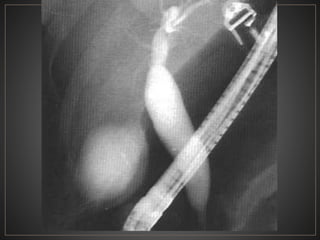

• #39 CPRE del mismo paciente corroborando la dilatación del coledoco en forma fusiforme, corresponde a un grado Ic

• #43 CPRE se observa a nivel intramural del coledoco una acumulación de medio de contraste, en relacion a un quiste tipo III